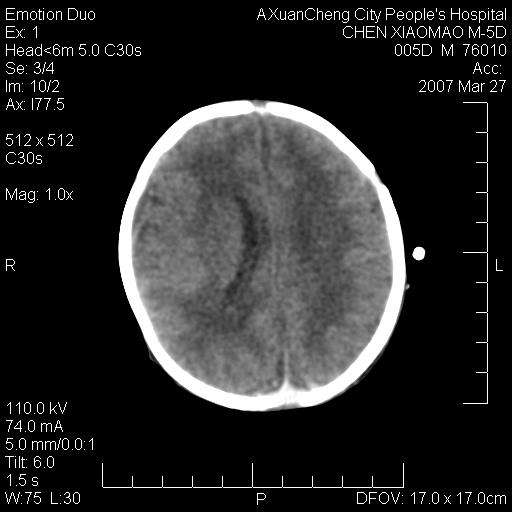

大家看看可有出血?另外枕骨中央是骨缝还是骨折

大家看看可有hie ?还有左侧枕部胡形高密度ct为45~53hu,可有硬膜下血肿?

左颞枕部有出血,枕骨有骨折

枕骨骨折可以下,应该比较明显,颅内还是正常的,不放心的话,短期随访。

未见明显异常,,那是横窦影,“缝”是后囟